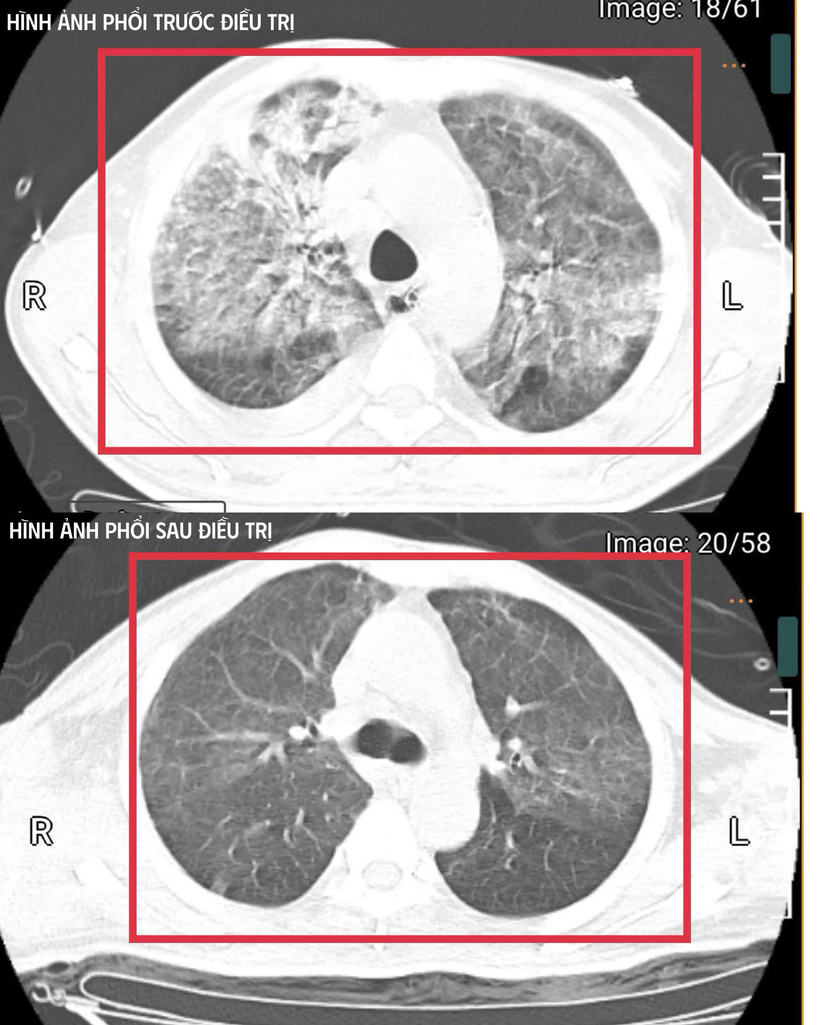

Sau khoảng ba ngày hồi sức cao độ, bệnh nhân bắt đầu cắt sốt, các chỉ số viêm giảm dần, huyết áp ổn định hơn với nhu cầu vận mạch giảm, chức năng gan thận cải thiện, tri giác dần hồi phục. Người bệnh cai được thở máy qua mở khí quản, tập lại hô hấp tự nhiên và phục hồi vận động. Trong ba tuần điều trị tích cực tại Khoa Cấp cứu, các bác sĩ tiếp tục tối ưu kháng sinh, kiểm soát chặt chẽ đường huyết, hỗ trợ dinh dưỡng và phục hồi chức năng sớm. Người bệnh hồi phục từng bước: tỉnh táo hoàn toàn, tự thở khí phòng với SpO₂ 99%, huyết áp 130/80 mmHg, cơ lực chi trên đạt 5/5, chi dưới 4/5, đủ điều kiện ra viện và tiếp tục theo dõi ngoại trú.